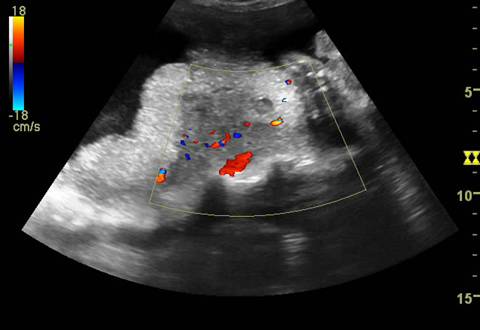

Arterele spiralate si placentomul. Dupa 28 sapt. mici ecouri anecogene rotunde apar in substanta placentara, reprezentand centrul placentomului - mica unitate de flux, unde se deschid artere spiralate. Cu ajutorul Doppler-ului color se poate urmari ejectia sangelui din arterele spiralate.

Vascularizatia uterina crescuta in trim. III, in peretele uterin nu trebuie confundata cu un hematom retroplacentar.

Fig nr.213 Vascularizatie a peretelui uterin subplacentara, ce nu trebuie confundata cu hematomul retroplacentar